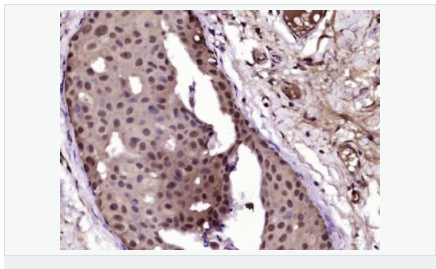

| 產(chǎn)品應(yīng)用 | WB=1:500-2000 IHC-P=1:100-500 IHC-F=1:100-500 Flow-Cyt=1ug/Test ICC=1:100-500 IF=1:100-500 (石蠟切片需做抗原修復(fù)) not yet tested in other applications. optimal dilutions/concentrations should be determined by the end user. |

| 細胞定位 | 細胞核 細胞漿 |

| 產(chǎn)品介紹 | Estrogen and progesterone receptor are members of a family of transcription factors that are regulated by the binding of their cognate ligands. The interaction of hormone-bound estrogen receptors with estrogen responsive elements(EREs) alters transcription of ERE-containing genes. The carboxy terminal region of the estrgen receptor contains the ligand binding domain, the amino terminus serves as the transactivation domain, and the DNA binding domain is centrally located. Two forms of estrogen receptor have been identified, ER alpha and ER beta. ER alpha and ER beta have been shown to be differentially activated by various ligands. The biological response to progesterone is mediated by two distinct forms of the human progesterone receptor (hPR-Aand hPR-B), which arise from alternative splicing. In most cells, hPR-B functions as a transcriptional activator of progesterone-responsive gene, whereas hPR-A function as a transcriptional inhibitor of all steroid hormone receptors. Function: The steroid hormones and their receptors are involved in the regulation of eukaryotic gene expression and affect cellular proliferation and differentiation in target tissues. Progesterone receptor isoform B (PRB) is involved activation of c-SRC/MAPK signaling on hormone stimulation. Isoform A is inactive in stimulating c-Src/MAPK signaling on hormone stimulation. Subunit: Interacts with SMARD1 and UNC45A. Interacts with CUEDC2; the interaction promotes ubiquitination, decreases sumoylation, and repesses transcriptional activity. Interacts with PIAS3; the interaction promotes sumoylation of PR in a hormone-dependent manner, inhibits DNA-binding, and alters nuclear export. Interacts with SP1; the interaction requires ligand-induced phosphorylation on Ser-345 by ERK1/2 MAPK. Interacts with PRMT2. Subcellular Location: Nucleus. Cytoplasm. Note=Nucleoplasmic shuttling is both homone- and cell cycle-dependent. On hormone stimulation, retained in the cytoplasm in the G(1) and G(2)/M phases. Isoform A: Nucleus. Cytoplasm. Note=Mainly nuclear. Post-translational modifications: Phosphorylated on multiple serine sites. Several of these sites are hormone-dependent. Phosphorylation on Ser-294 occurs preferentially on isoform B, is highly hormone-dependent and modulates ubiquitination and sumoylation on Lys-388. Phosphorylation on Ser-102 and Ser-345 also requires induction by hormone. Basal phosphorylation on Ser-81, Ser-162, Ser-190 and Ser-400 is increased in response to progesterone and can be phosphorylated in vitro by the CDK2-A1 complex. Increased levels of phosphorylation on Ser-400 also in the presence of EGF, heregulin, IGF, PMA and FBS. Phosphorylation at this site by CDK2 is ligand-independent, and increases nuclear translocation and transcriptional activity. Phosphorylation at Ser-162 and Ser-294, but not at Ser-190, is impaired during the G(2)/M phase of the cell cycle. Phosphorylation on Ser-345 by ERK1/2 MAPK is required for interaction with SP1. Sumoylation is hormone-dependent and represses transcriptional activity. Sumoylation on all three sites is enhanced by PIAS3. Desumoylated by SENP1. Sumoylation on Lys-388, the main site of sumoylation, is repressed by ubiquitination on the same site, and modulated by phosphorylation at Ser-294. Similarity: Belongs to the nuclear hormone receptor family. NR3 subfamily. Contains 1 nuclear receptor DNA-binding domain. SWISS: P06401 Gene ID: 5241 Database links: Entrez Gene: 5241 Human Entrez Gene: 18667 Mouse Entrez Gene: 100009094 Rabbit Omim: 607311 Human SwissProt: P06401 Human SwissProt: Q00175 Mouse SwissProt: P06186 Rabbit Unigene: 2905 Human Unigene: 32405 Human Unigene: 742403 Human Unigene: 12798 Mouse Unigene: 437703 Mouse Unigene: 1947 Rabbit Unigene: 10303 Rat Important Note: This product as supplied is intended for research use only, not for use in human, therapeutic or diagnostic applications. |